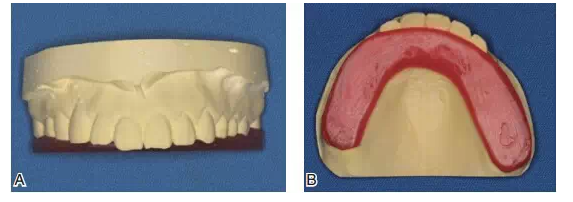

圖10該患者咬合重建修復(fù)前的關(guān)鍵是先確定牙合平面。A制作馬蹄型蠟板壓在上頜咬合面;B調(diào)整蠟板厚度和方向,用牙合平面板確定上頜牙合平面,牙合平面在前牙區(qū)和瞳孔連線平行,在后牙區(qū)和鼻翼耳屏面平行

圖11蠟板所代表的牙合平面

圖12在蠟板下方放置一個(gè)石膏平臺(tái)

圖13將上頜模型、蠟板、石膏平臺(tái)一起上平均值牙合架,取下蠟板后,在蠟板和石膏平臺(tái)之間留下的空隙內(nèi),用白色嵌體蠟雕刻后牙的牙冠形態(tài),形成恢復(fù)上頜正常牙合平面的診斷蠟型